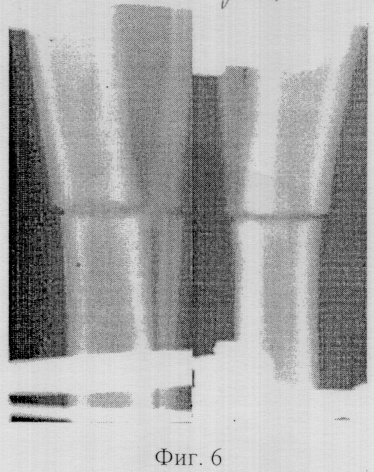

Фиг.6 – копия рентгенограммы костей голени согласно изобретению, 30 дней фиксации;

Через 30 дней фиксации у собак на рентгенограммах концы отломков имели нечеткие контуры. Наружные края их кортикальных пластинок были округлой формы. Межотломковая щель заметно увеличивалась. Последнюю перекрывали гомогенные тени низкой оптической плотности. Периостальные наслоения располагались с латеральной поверхности на концах обоих отломков в виде плотных образований толщиной 1,0-2,0 мм, не объединенных между собой. О наличии периостальной реакции также можно было судить по нечетким контурам наружных краев отломков на протяжении 1,0-1,5 см от линии остеотомии (Фиг 6).